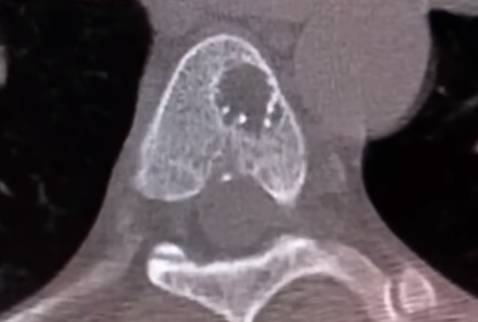

Онкопроцес може розвинутись на будь-якому рівні:

- шийний,

- грудний,

- поперековий

- чи крижовий відділ хребта.